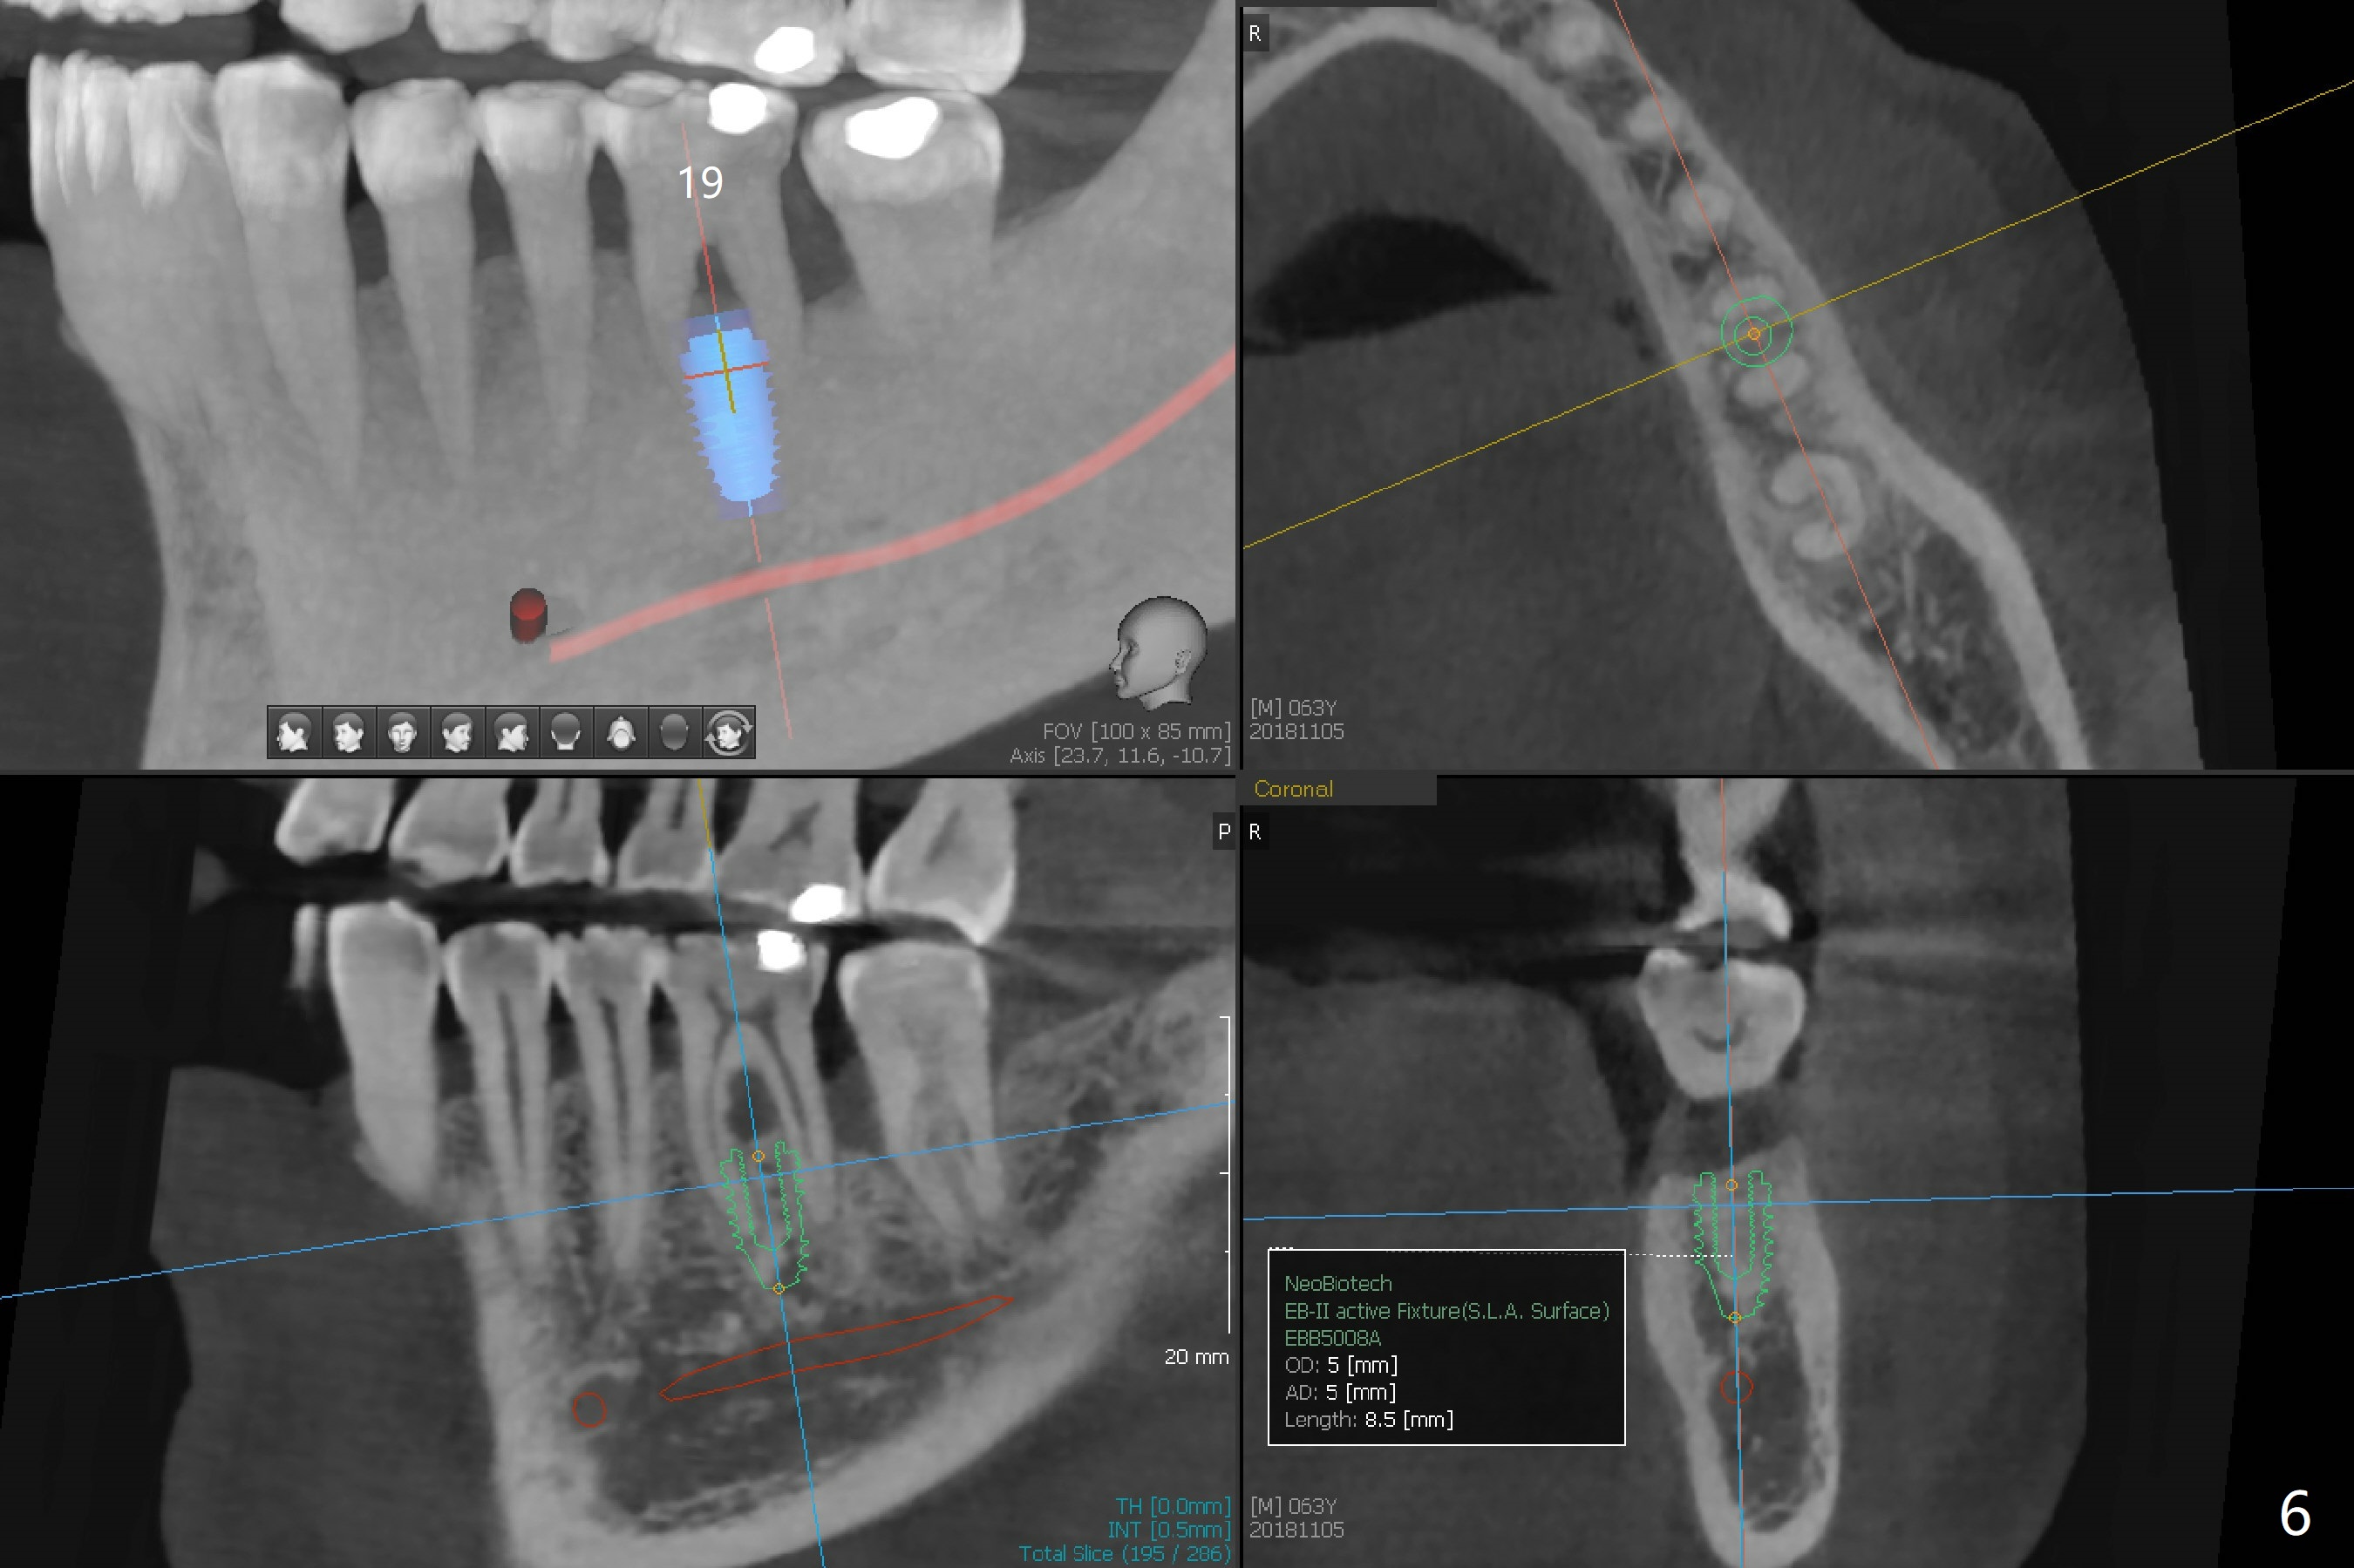

A 63-year-old man lives out of state and returns to office for scaling with chief complaint of occasional upper left pain (#14, Fig.1). After discussion, he agrees to have implant restoration in the upper right quadrant (#2-4). It appears that a 3-unit FPD is appropriate (Fig.2,3). When the teeth #14 and 19 fail, immediate implants will be placed (Fig.4-6).